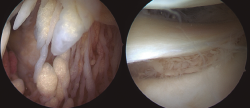

En los casos de la rodilla, con una intervención abierta (en el contexto de la colocación de una prótesis total de rodilla) y otra artroscópica, su localización fue predominantemente suprapatelar, si bien también se encontraron vellosidades (Figura 4).

Figura 4. Imágenes artroscópicas del LA en la rodilla, con presencia de vellosidades grasas en el receso suprapatelar e incluso en la zona supra- e inframeniscal.